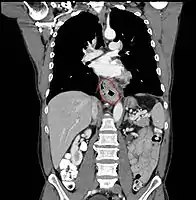

- AJCC divisions of the esophagus: (These are based on adjacent surgical landmarks)

- Cervical esophagus:

- Hypopharynx to the thoracic inlet, which is at the level of the sternal notch.

- By endoscopy, 15 to <20 cm from the incisors

- If thickening of the esophageal wall begins above the sternal notch, the location is cervical

- Upper thoracic esophagus:

- Thoracic inlet to lower border of the azygos vein

- By endoscopy, 20 to <25 cm

- Middle thoracic esophagus:

- Lower border of the azygos vein to the inferior pulmonary veins

- By endoscopy, 25 to <30 cm

- Lower thoracic esophagus and EG junction:

- Inferior pulmonary veins to the stomach; includes the intraabdominal portion of the esophagus

- By endoscopy, 30 to 40 cm